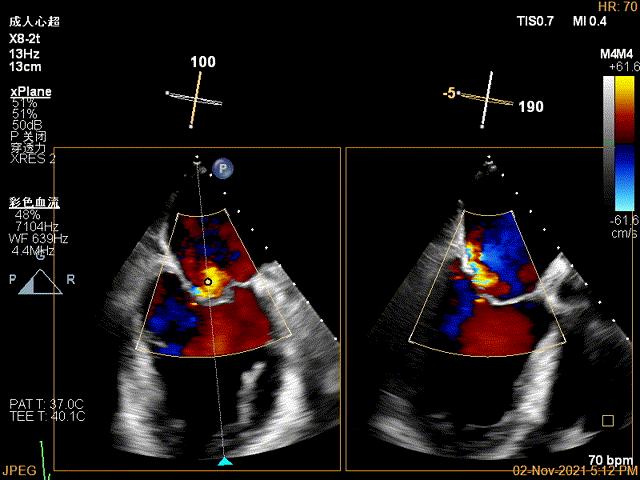

3D-color MV view:大量反流,起源于1区

3D视图下到达目标位置

3D视图下开夹子旋转使得clip的两个arm与MV对合线垂直

X-plane:下夹子尝试先捕获1区脱垂瓣叶

夹子关闭过程中,Color提示1区反流逐渐减少

3D证实夹子AC区残余脱垂被禁锢住

3D-color证实无明确残余分流